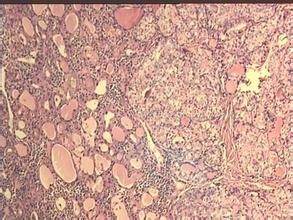

2.細胞免疫的證據是甲狀腺組織中有大量漿細胞和淋巴細胞浸潤和淋巴濾泡形成。有母細胞(blastcell)形成,移動抑制因子和淋巴細毒素的產生,本病患者的T淋巴細胞是有致敏活性的,相應的抗原主要是甲狀腺細胞膜。